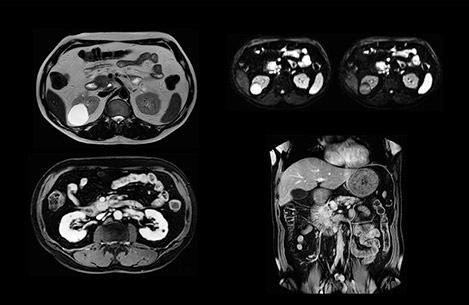

Dr. Baumann then implemented MultiVane XD for motion correction. It uses an extended reconstruction algorithm for imaging that is virtually motion free. “With MultiVane XD we get excellent motion-corrected images with high spatial resolution. We typically first optimize our scan for high image quality, and when satisfied with that, we try to reduce the scan time. So, we combined MultiVane XD with dS SENSE, which allows us to shorten the scan time,” he explains. “The performance of MultiVane XD in liver imaging is outstanding. MultiVane XD with dS SENSE is a powerful development in improving liver image quality.” “As we use breathhold imaging for T2-weighted liver scans, we depend on the patient’s ability to cooperate with the exam. This can present a real challenge when we are looking for small lesions, such as in our oncological patients. However, with MultiVane XD motion correction, we get excellent images. This is important for our surgeons, because they want to know exactly where the lesions are.”

In this example the image quality of the MultiVane XD images is evidently better than in the images without MultiVane XD. Ingenia 1.5T with dS Torso coil solution.

“Our liver exams are quite fast,” says Dr. Baumann. “If the patient tolerates it, we use an arms-up position to reduce the FOV and speed up the exam with dS SENSE.” “We acquire one transversal high resolution T2-weighted sequence with 3 mm slice thickness, for example for pancreas or liver lesions. Then we also add a T2 fat suppressed MultiVane XD SPIR sequence. We perform these two routinely in our liver imaging. We use high dS SENSE factors to significantly shorten scan times to 2-4 minutes, which can improve our protocol; it’s a very robust scan.” “We include mDIXON for the dynamic sequences because of the robust and homogeneous fat suppression we get with that. We had been using eTHRIVE, but we are now quite happy with mDIXON. Sometimes we use a medication to calm the bowels, to further improve the image quality.”

“We are more confident in our diagnosis if we don’t have to rescan the patient and compare it to other studies; this liver exam gives us good image quality in a faster time than the default system’s approach with arms down. That makes a difference for the patients, too. The shorter scan times, especially with the high dS SENSE factors, shorten the duration of the total examination. At the same time it’s more comfortable for the patient, to rest normally without holding the breath, just relaxing.”